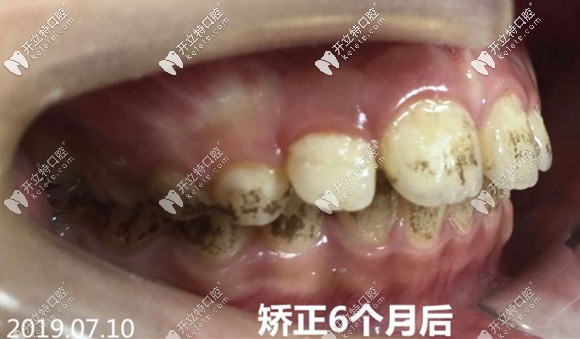

<矯治半年后的牙齒側(cè)貌~~~還好這位明智的家長(zhǎng)將孩子的齙牙凸嘴扼殺在萌芽期,僅僅半年就變化驚人>

矯治6個(gè)月后的牙齒側(cè)貌圖